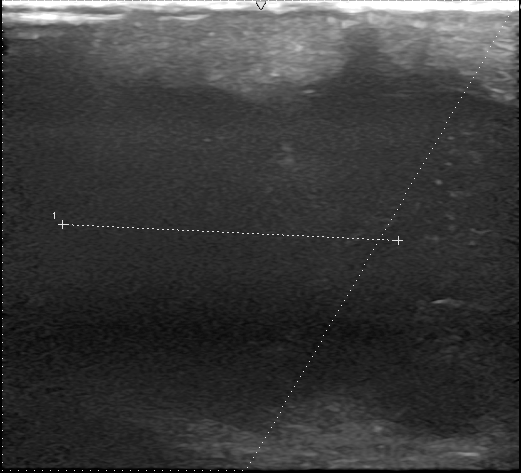

初回の再発

初回の再発を肉眼的には完全摘出